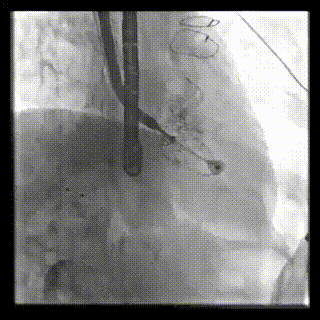

患者一术DSA

图片